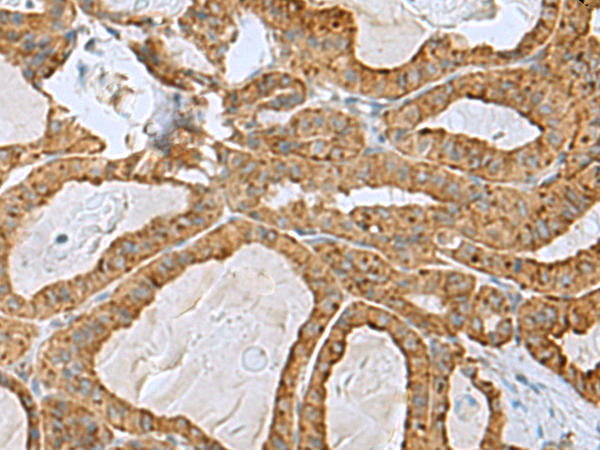

分类: 科研抗体货号: P10315别名: NDGOA; PARK5; PGP95; SPG79; PGP9.5; Uch-L1; HEL-117; PGP 9.5; HEL-S-53应用: WB,IHC反应种属: Human, Mouse, Rat

分类: 科研抗体货号: P10296别名:应用: IHC反应种属: Human, Mouse

分类: 科研抗体货号: P10330别名: EAPF; PHAFIN2; ZFYVE18应用: WB,IHC反应种属: Human, Mouse

分类: 科研抗体货号: P10314别名: p23; TMP21; p24d1; S31I125; Tmp-21-I; S31III125; P24(DELTA)应用: WB,IHC反应种属: Human, Mouse, Rat

分类: 科研抗体货号: P10295别名: COD3; GCAP; GUCA; GCAP1; GUCA1; CORD14; C6orf131应用: IHC反应种属: Human, Mouse

分类: 科研抗体货号: P10329别名: HDHD4; C20orf147; dJ694B14.3应用: IHC反应种属: Human, Mouse, Rat

分类: 科研抗体货号: P10313别名: RAB39应用: WB,IHC反应种属: Human, Mouse

分类: 科研抗体货号: P10294别名: ICAP1; ICAP1A; ICAP1B; ICAP-1A; ICAP-1B; ICAP-1alpha应用: IHC反应种属: Human, Mouse

分类: 科研抗体货号: P10328别名: PP2CE; PP2Ceta; PP2C-eta应用: IHC反应种属: Human, Mouse

分类: 科研抗体货号: P10312别名: L10A; CSA19; NEDD6; Csa-19应用: WB,IHC反应种属: Human, Mouse, Rat